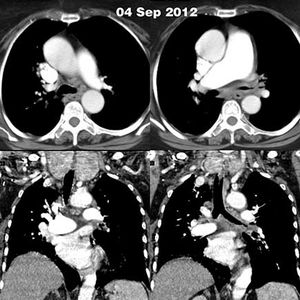

Case history: A 67-year-old female with a history of long standing goiter presented with a short onset history of cough and breathlessness. She did not have any fever or hemoptysis. The chest X-ray was unremarkable.